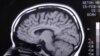

Алкоголь и мозг

Пьяному море по колено, гласит народная мудрость. Сотрудники американского Национального института по изучению алкоголизма подтвердили эту старую истину с помощью новейшей аппаратуры для сканирования мозга.

В их эксперименте участвовали 12 добровольцев. Каждому из них показали фотоснимки, на которых были изображены лица спокойных и до смерти перепуганных людей. Исследователи во главе с Джоди Гилман во время сеансов отслеживали активность их мозга с помощью функционального магнитно-резонансного томографа. В одной серии опытов испытуемым заранее вводили в вены разведенный спирт, а в другой – обычный физиологический раствор. Разумеется, сами участники не знали, что именно им колют: это было известно только экспериментаторам.

И вот что получилось. Мозг трезвых людей очень неодинаково реагировал на снимки разных типов. Если им показывали нейтральные фотографии, ответственные за обработку зрительной информации центры возбуждались куда слабее, нежели при демонстрации снимков угрожающего содержания. В то же время после внутривенной выпивки эти различия сильно смазывались.

Отсюда следует, что алкогольная интоксикация действительно ослабляет способность центральной нервной системы распознавать внезапные угрозы и адекватно на них реагировать. Так что феномен пьяной удали теперь получил физиологическое объяснение. Обо всем этом говорится в статье, которую опубликовал Journal of Neuroscience.